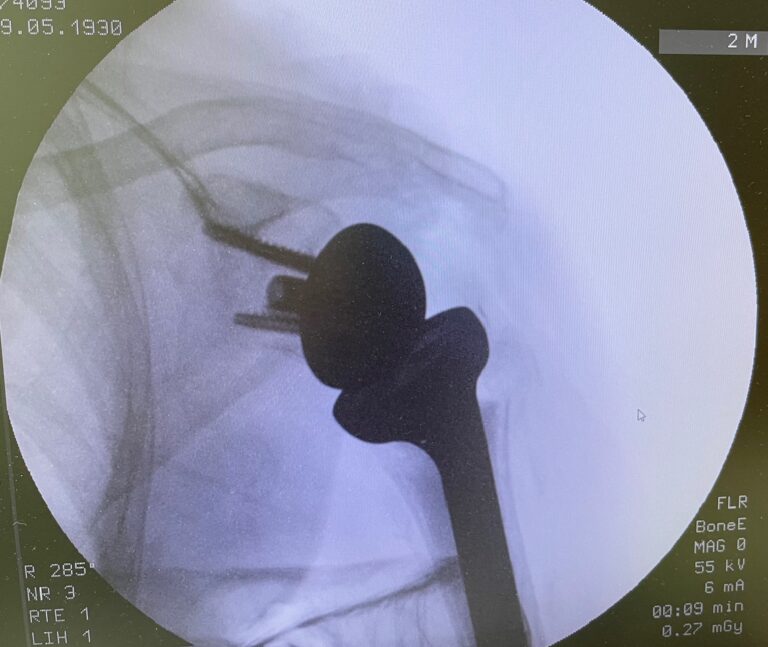

Η ανάστροφη ολική αρθροπλαστική ώμου είναι μια εξειδικευμένη χειρουργική επέμβαση αντικατάστασης της άρθρωσης του ώμου, η οποία εφαρμόζεται κυρίως σε ασθενείς με σοβαρή βλάβη του στροφικού πετάλου και εκφυλισμό της άρθρωσης.

Σε αντίθεση με την κλασική αρθροπλαστική, αλλάζει τη μηχανική του ώμου, επιτρέποντας στο χέρι να κινείται κυρίως με τη δύναμη του δελτοειδούς μυός.

Τι σημαίνει «ανάστροφη» αρθροπλαστική;

Στην ανάστροφη αρθροπλαστική:

- Η κεφαλή τοποθετείται στην ωμογλήνη

- Η κοίλη επιφάνεια τοποθετείται στο βραχιόνιο

Αυτή η αναστροφή επιτρέπει στον δελτοειδή μυ να αναλάβει την κίνηση του ώμου, όταν το στροφικό πέταλο δεν λειτουργεί.

- Περιλαμβάνει τοποθέτηση ειδικής πρόθεσης ώμου